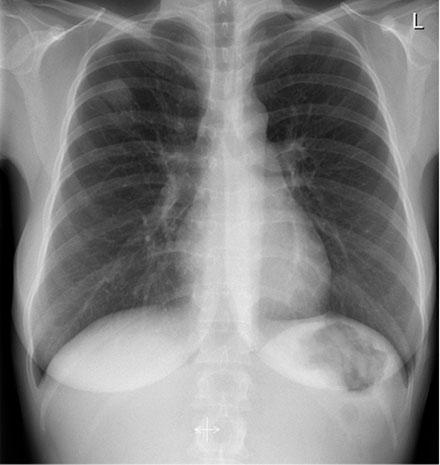

Chest X-ray of a smear-negative, culture-positive TB case detected from screening. A small,

opa-que infiltrate is observed in the right upper lobe. It resolved completely during treatment and may represent early-

stage TB.

Incidence of LTBI varied considerably between locations: 27.7% (5/18) at one shelter and 60% (3/5) at a common house outside the city centre; 14.6% (7/48) and 3.4% (1/29) at two other shelters. The incidence of LTBI by location generally reflected the ethnicity of the subjects, being mainly Greenlandic at the two high-incidence locations. Of the 124 sputum samples collected, none were smear-positive, but one was culture-positive for M. tuberculosis: a 36-year-old woman of Greenlandic origin (Figure 1).

The participant with TB had discrete symptoms, no pathology on the chest X-ray, and was smear-negative. The culture turned positive after several weeks. We therefore assume that she was at an early stage of disease, and it seems likely that she would not have presented herself for examination until several months later in a passive case-finding setting. As active disease transmission is ongoing in this environment, early detection of a few TB cases most likely contributes to improved TB control by preventing secondary cases.